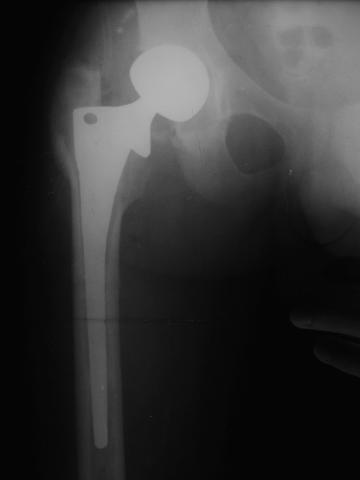

Уважаемые коллеги!молодой человек 22 лет обратился к нам с жалобами на умеренную боль в в/3 левого бедра и паху при ходьбе, укорочение левой ноги. 3 года назад получил закрытый перелом шейки левого бедра (рис 1).

Лечился в стержневом аппарате по месту жительства. АВФ демонтировали через полгода из-за воспаления в области стержней (рис 2). После демонтажа в течение месяца больной лихорадил до 38*, были боли в бедре. Эти явления исчезли после курса антибиотиков. Через год после травмы в ЦРБ ему имплантировали биполярный протез (рис 3). Рана зажила первично. Ходил с костылями, слегка приступая на ногу. На контрольных осмотрах выявлена прогрессирующая протрузия (рис 4-6).